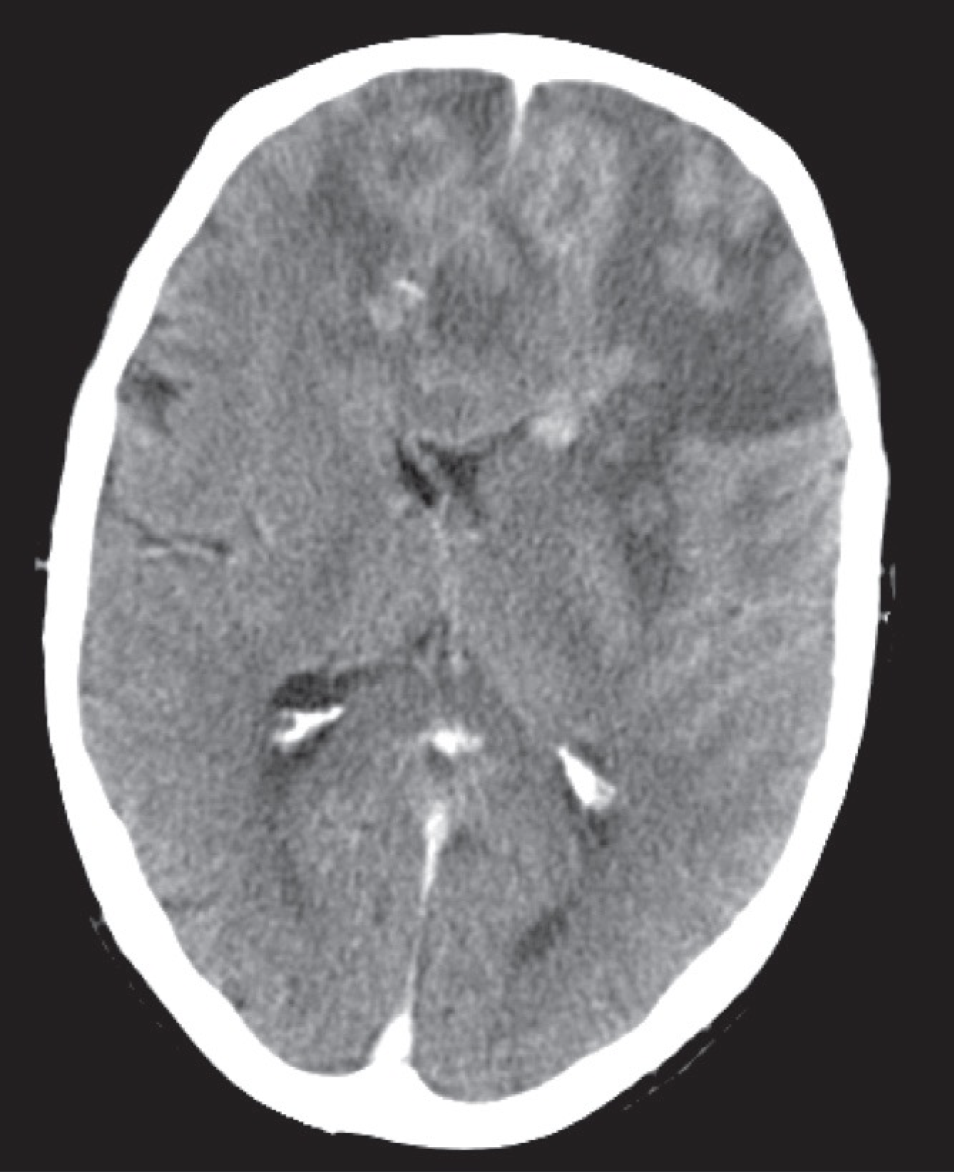

CT scan, post intravenous contrast,

showing an irregular enhancing mass with surrounding low attenuation involving both frontal lobes and the corpus callosum, in keeping with a high grade glioma (glioblastoma multiforme).

Bilateral glioblastoma (butterfly glioma)